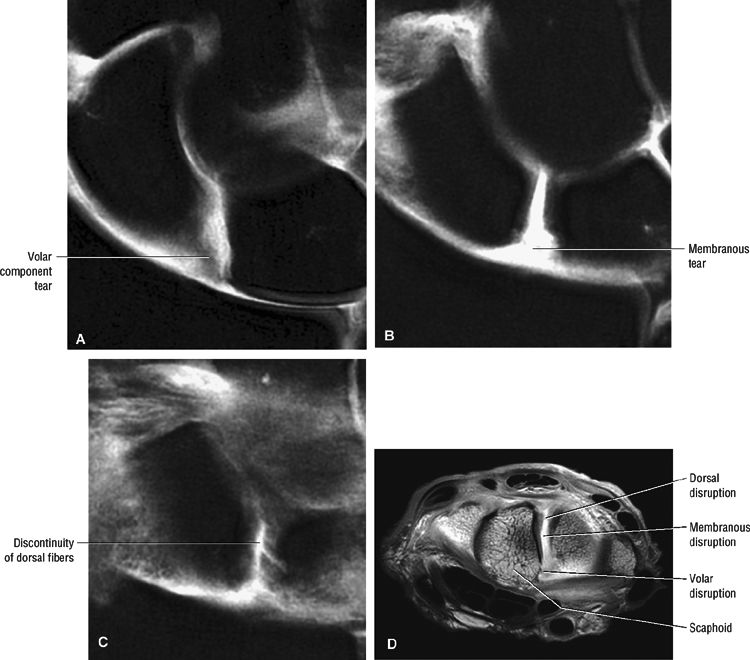

All three components of the scapholunate ligament should be evaluated on coronal and axial images.

Dorsal component scapholunate ligament tears are more likely to be symptomatic.

Disruption of the scapholunate ligament is shown on T2*-weighted or STIR images as either complete ligamentous disruption or as a discrete area of linear hyperintensity in a partial or complete tear (Fig. 10.90).

In complete tears, synovial fluid communication between the radiocarpal and midcarpal compartments may be identified. Associated stretching (i.e., redundancy) or tearing of the radiolunate ligament and the radioscaphocapitate ligament is shown on sagittal images.

A flap tear may not be appreciated without the use of MR arthrography. MR arthrography is also helpful in evaluation of perforations and integrity of the dorsal component of the scapholunate ligament.

A perforation, identified by communication of fluid across a focal discontinuity, constitutes a communicating defect or tear. Small membranous perforations may exist in the presence of intact dorsal and volar portions of the scapholunate ligament. In fact, most degenerative perforations occur in the thin membranous portion of the scapholunate ligament, which is not thought to be biomechanically significant.59,60

Partial-thickness perforations or noncommunicating defects may be associated with ligamentous tissue degeneration or sprains and may be difficult to appreciate on MR images.61

A complete scapholunate ligament tear may not be associated with scapholunate interval diastasis or static carpal instability as assessed on sagittal images, especially when the volar extrinsic ligaments are intact.

Axial MR images are used to distinguish among tears of the dorsal, membranous, and volar portions of the scapholunate ligament. The location of the tear can then be directly correlated with dorsal or volar coronal images.

The scaphoid attachment of the scapholunate ligament is more likely to avulse than is the stronger lunate attachment.59 The insertion of the scapholunate ligament into hyaline cartilage covering the scaphoid is thus relatively weak. In fact, a scapholunate ligament

tear may be associated with a scaphoid avulsion fracture (Fig. 10.91). -

Potential sites of injury of the intrinsic scapholunate ligament complex (the scapholunate interosseous ligament) (Fig. 10.92) include its dorsal component (an important key stabilizer), a membranous component, and a volar component.